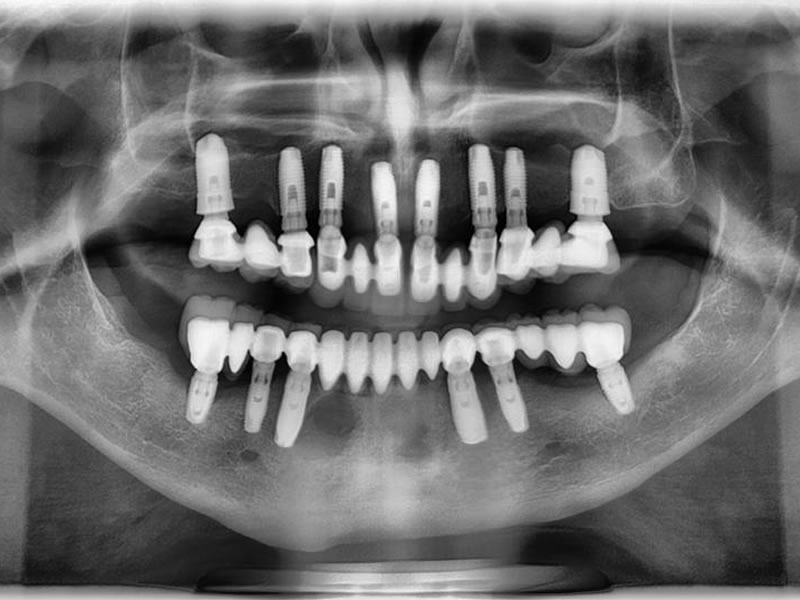

La implantología, es sin duda alguna la rama de la odontología con avances y predictabilidad más impactante hoy en día. Solo con el hecho de explorar posibilidades protesicas que eliminen el uso de "placas" o prótesis ...

Leer más